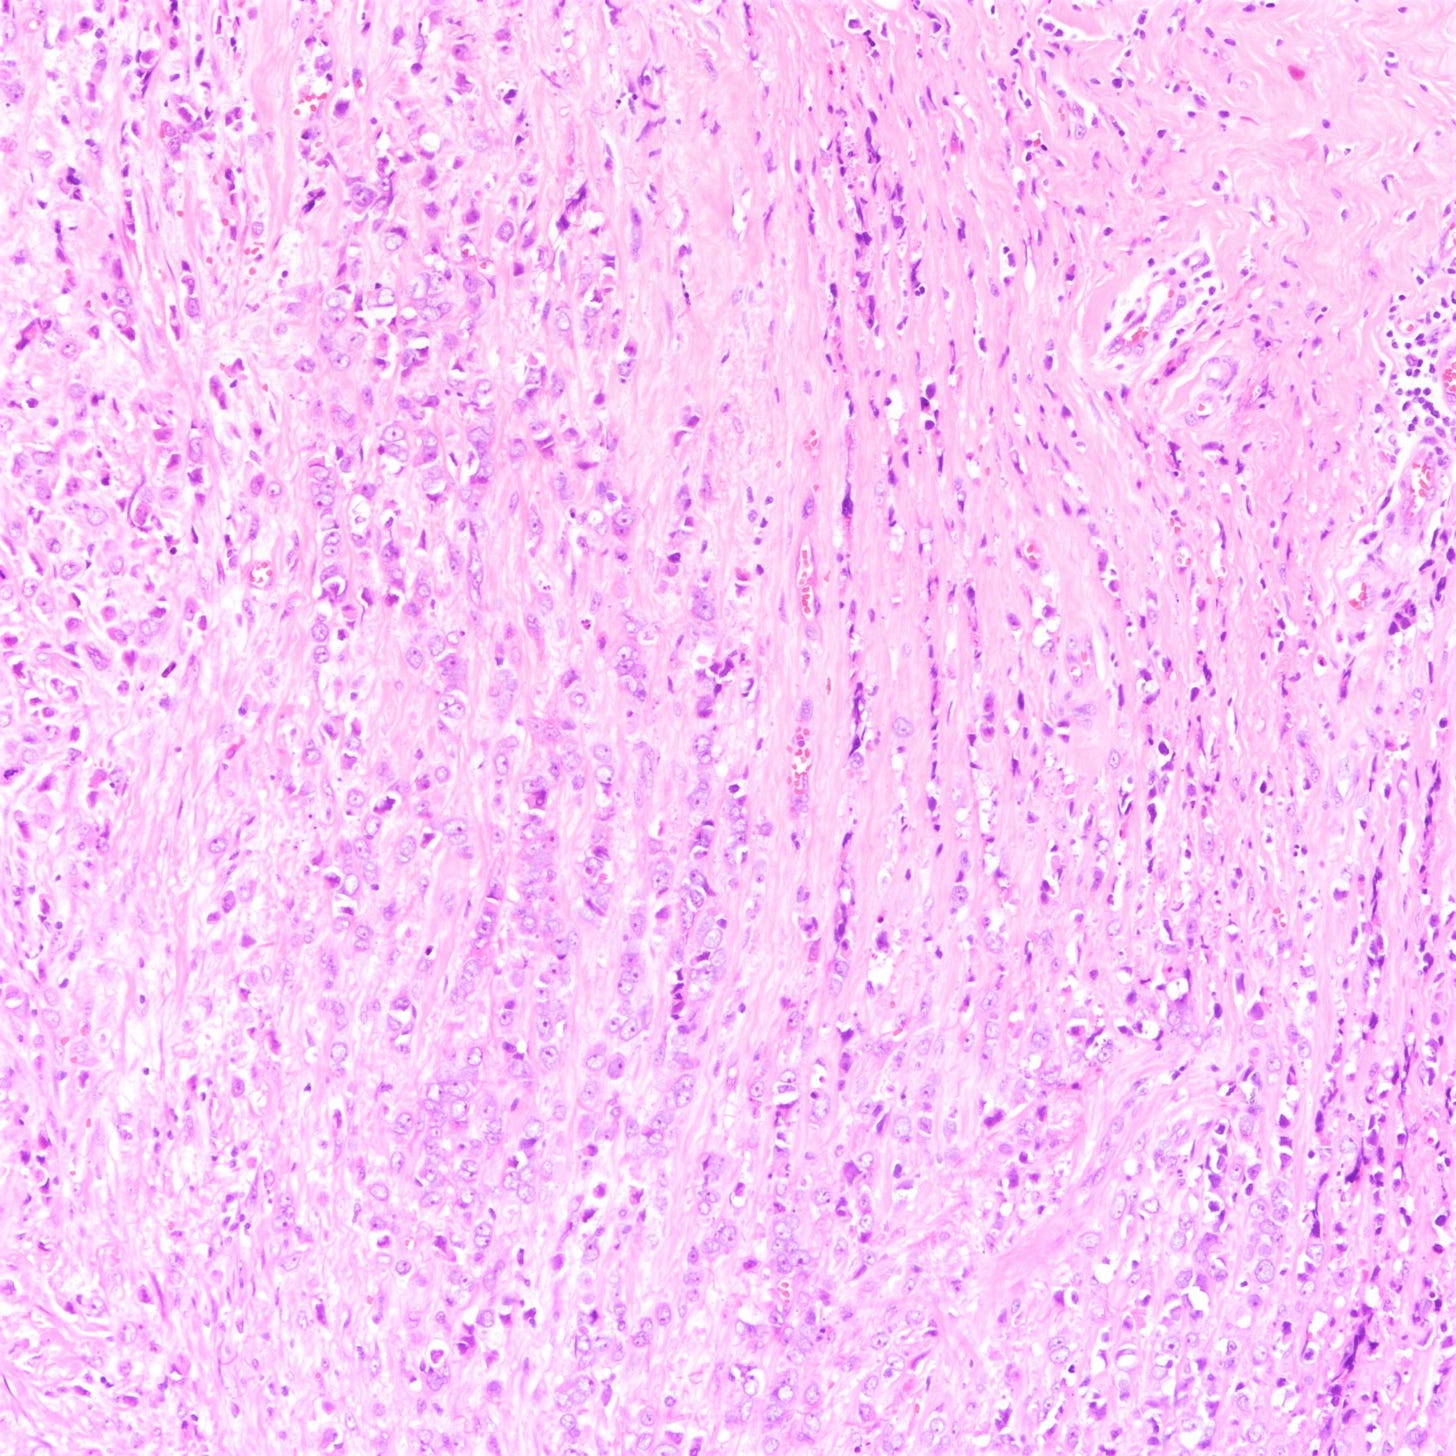

Lobular carcinoma

Lobular carcinoma is a common type of invasive breast carcinoma (10% of cases). It is characterized by the loss of cellular adhesion with dyscohesive tumor cells arranged in single file or as individual single cells. The cells show a loss of 16q (the CDH1 gene located at 16q22.1 encodes E-cadherin, essential in forming the adherens junction responsible for cell adhesion). Loss of E-cadherin protein expression by immunohistochemistry is helpful but not required for diagnosis.

Lobular carcinoma of the breast typically presents with vague findings such as thickening, swelling or a poorly defined breast mass. In general, it is more difficult to detect with mammography (due to infrequent calcifications) and more often presents as a larger tumor with nodal involvement compared to invasive ductal carcinoma of no special type. It is more frequently bilateral and multifocal.

A mastectomy may be preferred because of the risk of local recurrence. These patients generally respond better to hormonal therapy compared to those with invasive ductal carcinoma of no special type. However, their response to radiation therapy is comparable, while their response to chemotherapy is less favorable

Classic lobular carcinoma - microscopic images

The premalignant precursors of classic lobular carcinoma are classic lobular carcinoma in situ (classic LCIS), its variants florid LCIS and pleomorphic LCIS, and atypical lobular hyperplasia (ALH).